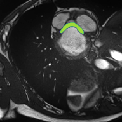

Despite their outstanding accuracy, semi-supervised segmentation methods based on deep neural networks can still yield predictions that are considered anatomically impossible by clinicians, for instance, containing holes or disconnected regions. To solve this problem, we present a Context-aware Virtual Adversarial Training (CaVAT) method for generating anatomically plausible segmentation. Unlike approaches focusing solely on accuracy, our method also considers complex topological constraints like connectivity which cannot be easily modeled in a differentiable loss function. We use adversarial training to generate examples violating the constraints, so the network can learn to avoid making such incorrect predictions on new examples, and employ the Reinforce algorithm to handle non-differentiable segmentation constraints. The proposed method offers a generic and efficient way to add any constraint on top of any segmentation network. Experiments on two clinically-relevant datasets show our method to produce segmentations that are both accurate and anatomically-plausible in terms of region connectivity.